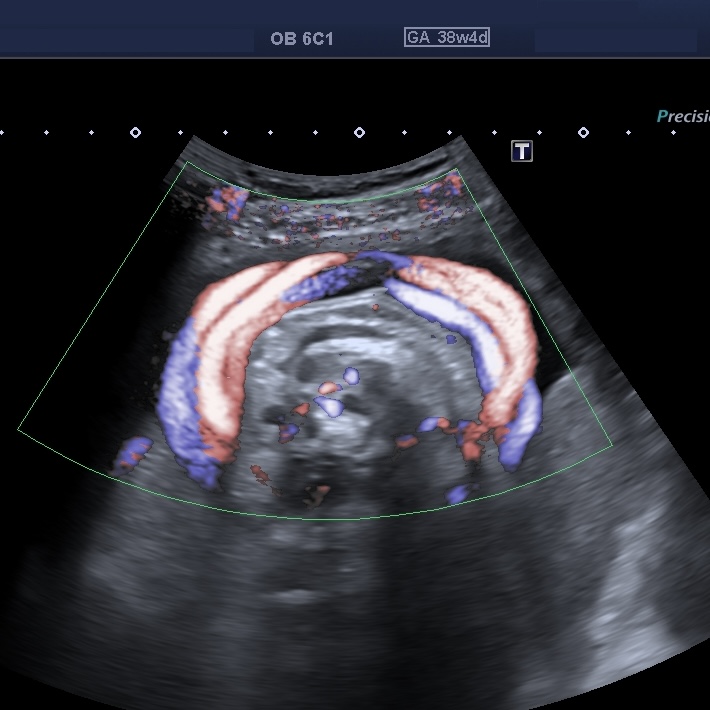

Se presenta el caso de una paciente primigesta, cursando un embarazo de 38 semanas de gestación, sin antecedentes de relevancia. Acude a la consulta para realizar una ecografía obstétrica con Doppler obstétrico. Refiere que, de mantenerse condiciones obstétricas favorables, se planificará un parto domiciliario. Hallazgos ecográficos: ? Feto único vivo, en presentación cefálica. ? Biometría acorde a la edad gestacional. ? Líquido amniótico dentro de parámetros normales. ? Placenta normoinserta. ? Doppler obstétrico dentro de rangos normales en todos los trayectos estudiados. A nivel del cuello fetal se observa las siguientes imágenes: Ante este hallazgo ecográfico usted: A) Interpreta doble circular de cordón y no la describe en el informe, ya que su presencia antenatal no modifica la conducta obstétrica ni predice por sí sola resultados adversos. B) Describe la doble circular de cordón umbilical como hallazgo ecográfico objetivo, especificando método diagnóstico, sin emitir recomendaciones obstétricas adicionales. C) Describe el hallazgo como circular de cordón múltiple e indica en el informe sugerencia de finalización institucional del embarazo debido al potencial riesgo intraparto.